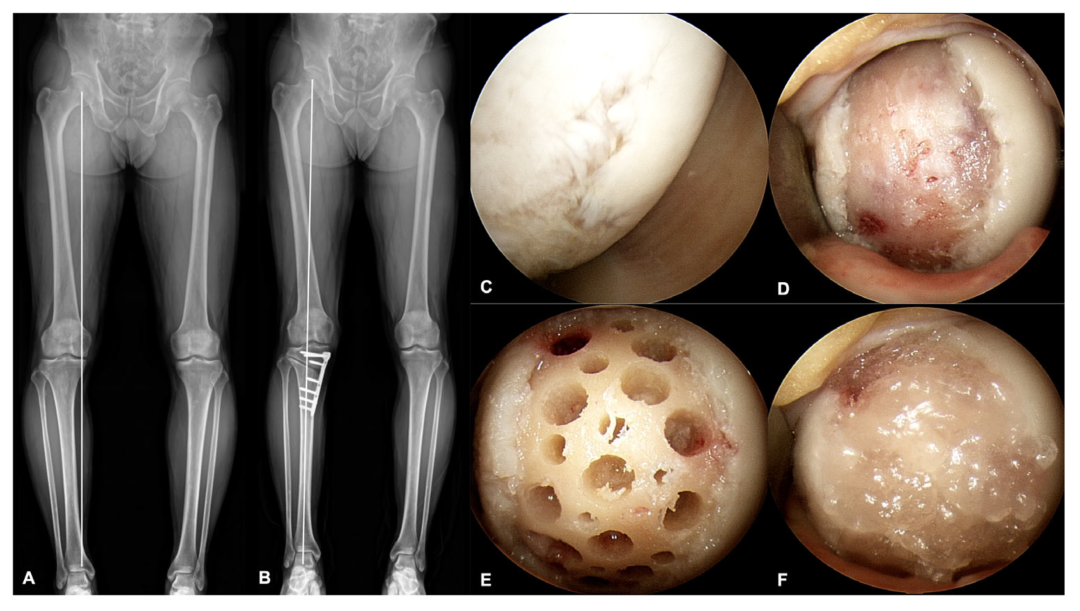

脐血干细胞治疗膝骨关节炎

韩国首尔中央大学医学院的整形外科医生开展的一项研究中,12名全层软骨缺损的膝关节内侧关节炎患者入组,接受了脐带血干细胞、透明质酸盐复合材料联合胫骨高位截骨术的治疗。在平均2.9年的随访中,所有临床结果均有所改善,80%患者的整体修复水平被评估为“正常”或“接近正常”。